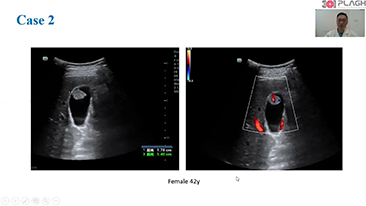

Opieka oparta mniej na stetoskopie, a bardziej na USG?

Zoptymalizowane schematy post?powania w badaniach ginekologicno-po?o?niczych s? niezb?dne, aby obs?u?y? du?? liczb? wizyt przesiewowych w poradniach zdrowia dla kobiet. Dla przyk?adu deformacje o?rodkowego uk?adu nerwowego (OUN) to jedne z najcz?stszych wad wrodzonych. Ze wzgl?du na r├│?ne warunki obrazowania, takie jak niewystarczaj?co dobra pozycja p?odu, obrazowanie ?rodkowej p?aszczyzny strza?kowej (MSP, median sagittal plane) jest szczeg├│lnie trudno uzyska? na podstawie klasycznego obrazu USG 2D. Dlatego automatyczne wykrywanie i pomiary mog? znacz?co poprawi? efektywno?? skanowania.